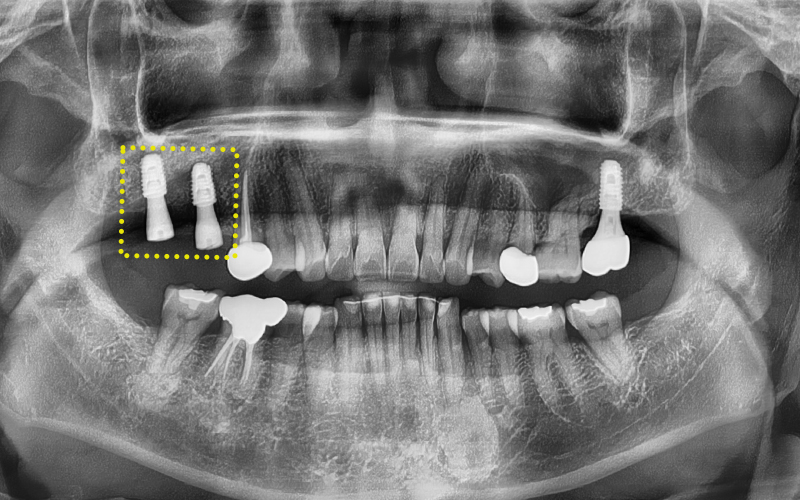

✅ 엑스레이로 본 문제점

그리고 엑스레이와 CT 사진을 촬영해

구강 내 상황을 정밀하게 체크해보았는데요.

엑스레이를 보시더니 환자분께서도

제가 봐도 너무 뒤쪽에 심긴 것 같다는

말씀을 해주셨답니다.

확인 결과, 상악동 거상술을

두 차례 시도했지만 실패했고,

결국 사랑니 위치처럼

뒤쪽에 임플란트가 식립된 상태였습니다.

임플란트 자체는 골유착이 잘 되어 있었지만,

명확한 위치가 아니어서

보철물 제작이 매우 불리한 상황이었답니다...!

게다가 앞쪽에 있는 신경치료 중인 치아는